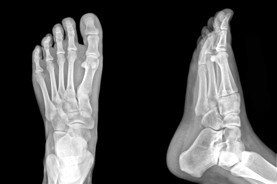

At the Red Deer Foot Institute, our Doctors are trained to specifically treat problems associated with your feet or ankles. Below are several of the most common problems that we see on a day to day basis: